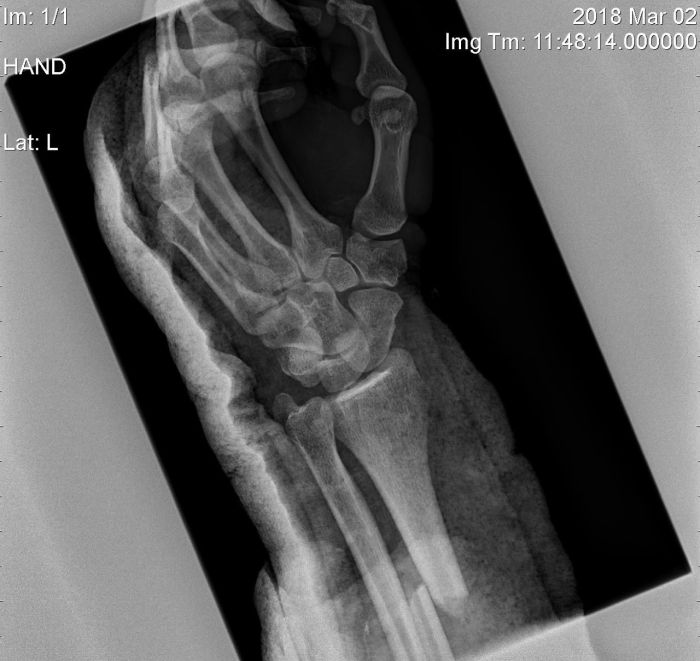

Operace ruky - 22.5.2019